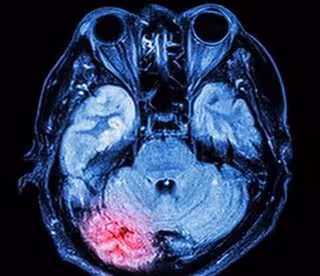

Archivo - La zona roja muestra el lugar donde se inflama el cerebro después de una conmoción cerebral.

Archivo - La zona roja muestra el lugar donde se inflama el cerebro después de una conmoción cerebral. - UNIVERSITY OF SOUTH AUSTRALIA - Archivo